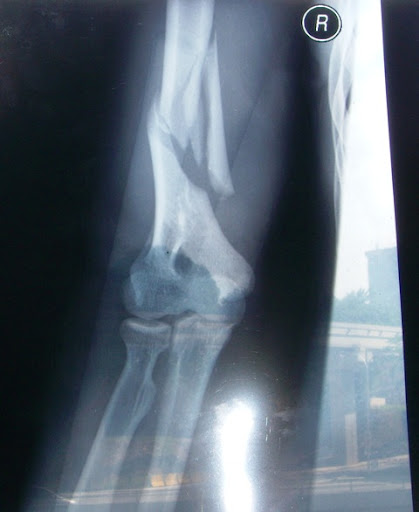

Broken arm of a Zomi refugee. Zo Taang fall down from the lorry he was driving and his Right arm was broken.